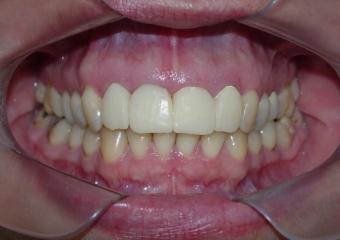

Sorriso final, do caso terminado em abril de 2013